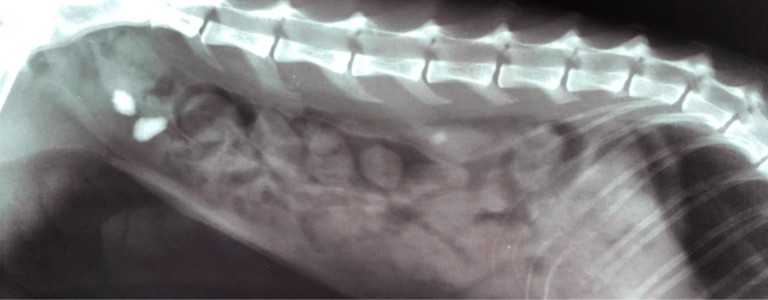

- Une échographie ou radiographie est souvent recommandée pour localiser et mesurer les calculs.